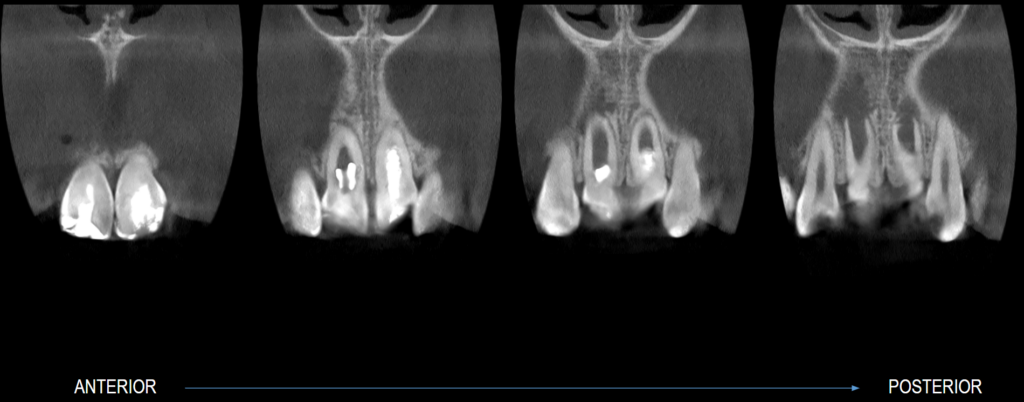

En la tomografía computarizada de haz cónico (CBCT) de campo reducido, evaluada en cortes axiales (Figura 2), coronales (Figura 3) y transaxiales (Figuras 4 y 5), se observa formación radicular incompleta, caracterizada por un conducto radicular amplio en los tercios medio y apical, así como un foramen apical de gran diámetro, asociado a un proceso osteolítico periapical difuso.

Adicionalmente, en la pieza 11 se identifica una imagen hipodensa de morfología tubular que se extiende desde el tercio cervical radicular hasta la superficie vestibular, provocando la pérdida de continuidad de la pared radicular, compatible con una perforación radicular iatrogénica. Se observa también pérdida de continuidad de la corona protésica, presencia de espigo-muñón y obturación

endodóntica del conducto.

CORTES CORONALES